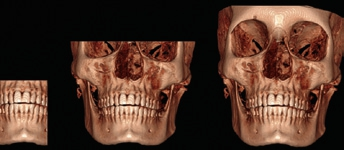

- Die digitale Volumentomographie (DVT) liefert die höchste Auflösung von knöchernen Strukturen, die Darstellung und/oder Differenzierung von Weichgewebe ist jedoch nicht möglich. Vorteile sind die geringen Kosten und die im Vergleich zur CT reduzierten Metallartefakte. Nachteilig hingegen sind der geringe Weichteilkontrast und die Gewebedifferenzierung (Abb. 2 u. 3).

Durch weitere Rechenprozesse können die Daten auf verschiedenste Weise dargestellt werden. Die multiplanaren Rekonstruktionen (MPR) stellen die sinnigste Weiterverarbeitung der Daten dar. Hierbei wird das Volumen durch senkrecht zueinander stehende Ebenen zerlegt, wodurch die Ansichten axial, sagittal und koronal erzeugt werden, ergänzt durch die oberflächengerenderte Ansicht (Abb. 9). Das Angebot entsprechender Bildbearbeitungsprogramme ist vielfältig, zumeist wird das DVT-Gerät mit einer adäquaten Software installiert und eingerichtet – ab diesem Zeitpunkt ist nun der/die Anwender/-in gefordert. In Deutschland ist die Absolvierung eines DVT-Kurses vor Inbetriebnahme eines DVT-Gerätes gesetzlich vorgeschrieben.